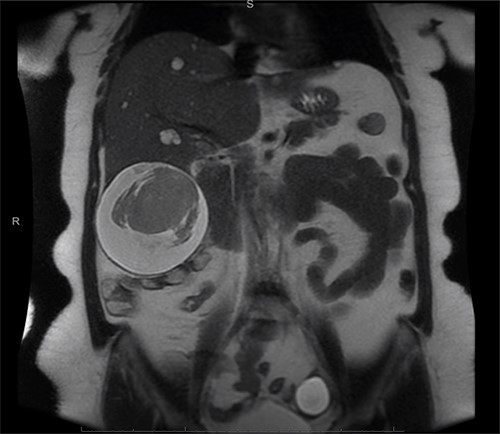

A computed tomography (CT) scan with intravenous (IV) contrast of the abdomen (Fig. 1) was performed and demonstrated a large 12 × 11 × 10 cm round exophytic complex hepatic cyst containing central soft tissue density mass and septations with multiple small hepatic cysts throughout liver. A hemorrhagic component within the cyst was also seen. In order to further delineate the cyst’s relationship to the biliary tree and surrounding structures, magnetic resonance imaging (Fig. 2) was also performed and a large exophytic peripherally cystic lesion with central solid non-enhancing component in inferior right lobe of the liver was seen. There was no evidence to suggest free rupture, communication to the biliary tree or hemobilia. The patient was admitted for close monitoring and on the third day her abdominal examination progressed to include tenderness in all quadrants of the abdomen with peritoneal signs. The patient received two packed red blood cell transfusions due to a drop in hemoglobin (12.1–8.8 g/dl) associated with tachycardia up to 131 bpm. Surgical management was discussed with the patient and she agreed to proceed.

Abdominal CT scan showing a large cyst 12 × 11 × 10 cm in the right hepatic lobe with a hemorrhagic component.